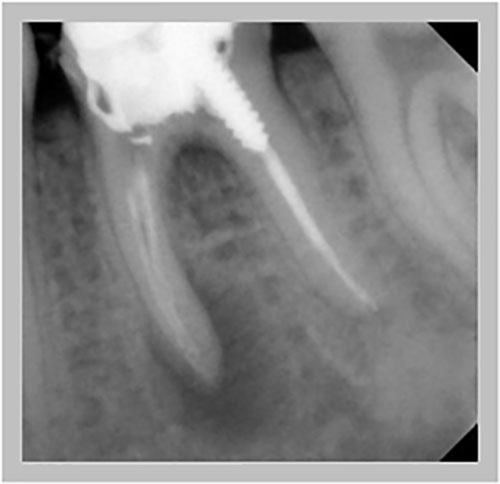

Χρόνια φλεγμονώδης περιακρορριζική βλάβη, κυρίως,

λόγω ενδοδοντικής αιτιολογίας. Μετά την ενδοδοντική θεραπεία

ακολούθησε περιοδοντική θεραπεία.

Δύο χρόνια μετά, παρατηρείται πλήρης εξαφάνιση της βλάβης.